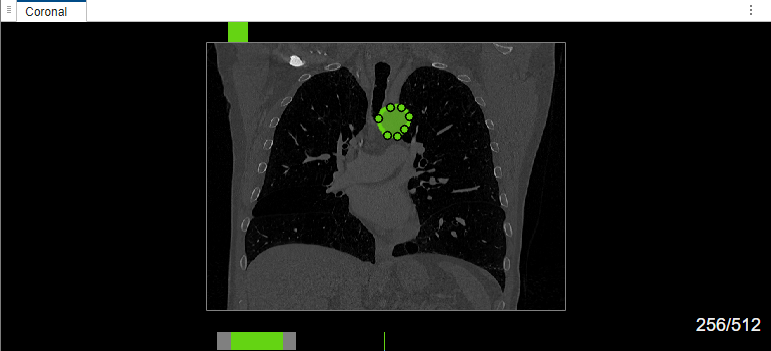

Edit Labels Created Using MedSAM

Select label Type2. Draw a bounding box around the object to segment in the coronal plane of the volume. The MedSAM algorithm extracts the embeddings of the image and segments the object in the bounding box. Right-click the labeled object, and, from the context menu, select Select Drawn Region. You can now edit the label shape using the points, or reassign or delete the label by using the options in the context menu.